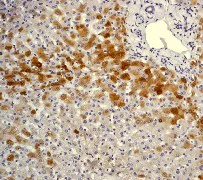

Immunohistochemistry (Formalin/PFA-fixed paraffin-embedded sections) - Anti-C Reactive Protein antibody [Y284] (AB32412)

Immunohistochemical analysis of formalin fixed paraffin embedded human liver labelling C Reactive Protein with ab32412 at a concentration of 0.01µg/ml. The immunostaining was performed on a Ventana DISCOVERY ULTRA (Roche Tissue Diagnostics) instrument with a OptiView DAB IHC Detection Kit. Heat mediated antigen retrieval was performed with DISCOVERY cell conditioning solution (CC1) 100°C, pH8.5 for 32 mins. ab32412 anti-C Reactive Protein antibody [Y284] was incubated for 16 mins at 37°C. Sections were counterstained with Hematoxylin II. Image inset shows absence of staining in secondary antibody only control.

Customers are encouraged to optimise antigen retrieval conditions, antibody concentration, incubation times and temperature for best results in their own IHC assay workflow (automated and manual).